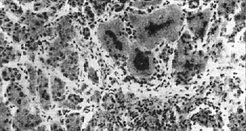

![]() Рис. 13. Застійне повнокров'я печінки. Атрофія печінкових пластинок до повного їх зникнення. Центральний некроз часточки (X150). |

Некрози П. розрізняють в залежності від локалізації їх всередині часточки. Центральні некрози можуть бути обумовлені токсичними факторами, застійним полнокровием (рис. 13), перешкодами току крові з ворітної вени і печінкової артерії, алергічними факторами та ін.

Застійне (пасивне) повнокров'я печінки найчастіше є результатом підвищення тиску в системі нижньої порожнистої вени у зв'язку з розладом серцевої діяльності. П. збільшена, капсула напружена, передній край тупий, ложе жовчного міхура набряково; на розрізі - підкреслений малюнок часточок. Мікроскопічно: центральні вени і прилеглі капіляри розширені, заповнені кров'ю, печінкові пластинки розсунуті, здавлені, ретикулиновая строма збережена. При підгострому застійному полнокровии П. зменшена, краї її гострі. На розрізі - центр часточок темно-червоний, запалий, периферія - жовто-коричнева (мускатна печінка). Мікроскопічно: печінкові пластинки в центрі часточок атрофовані, іноді до повного зникнення (рис. 13). Хронічне застійне повнокров'я П. супроводжується застійної индурацией (мускатний фіброз печінки). П. щільна, капсула потовщена, ложе жовчного міхура склерозировано. Мікроскопічно: коллагенизация коллабированных ретикулиновых волокон у спустошених (загибель гепатоцитів) центрах часточок; потовщення та склероз центральних вен, портальний фіброз.